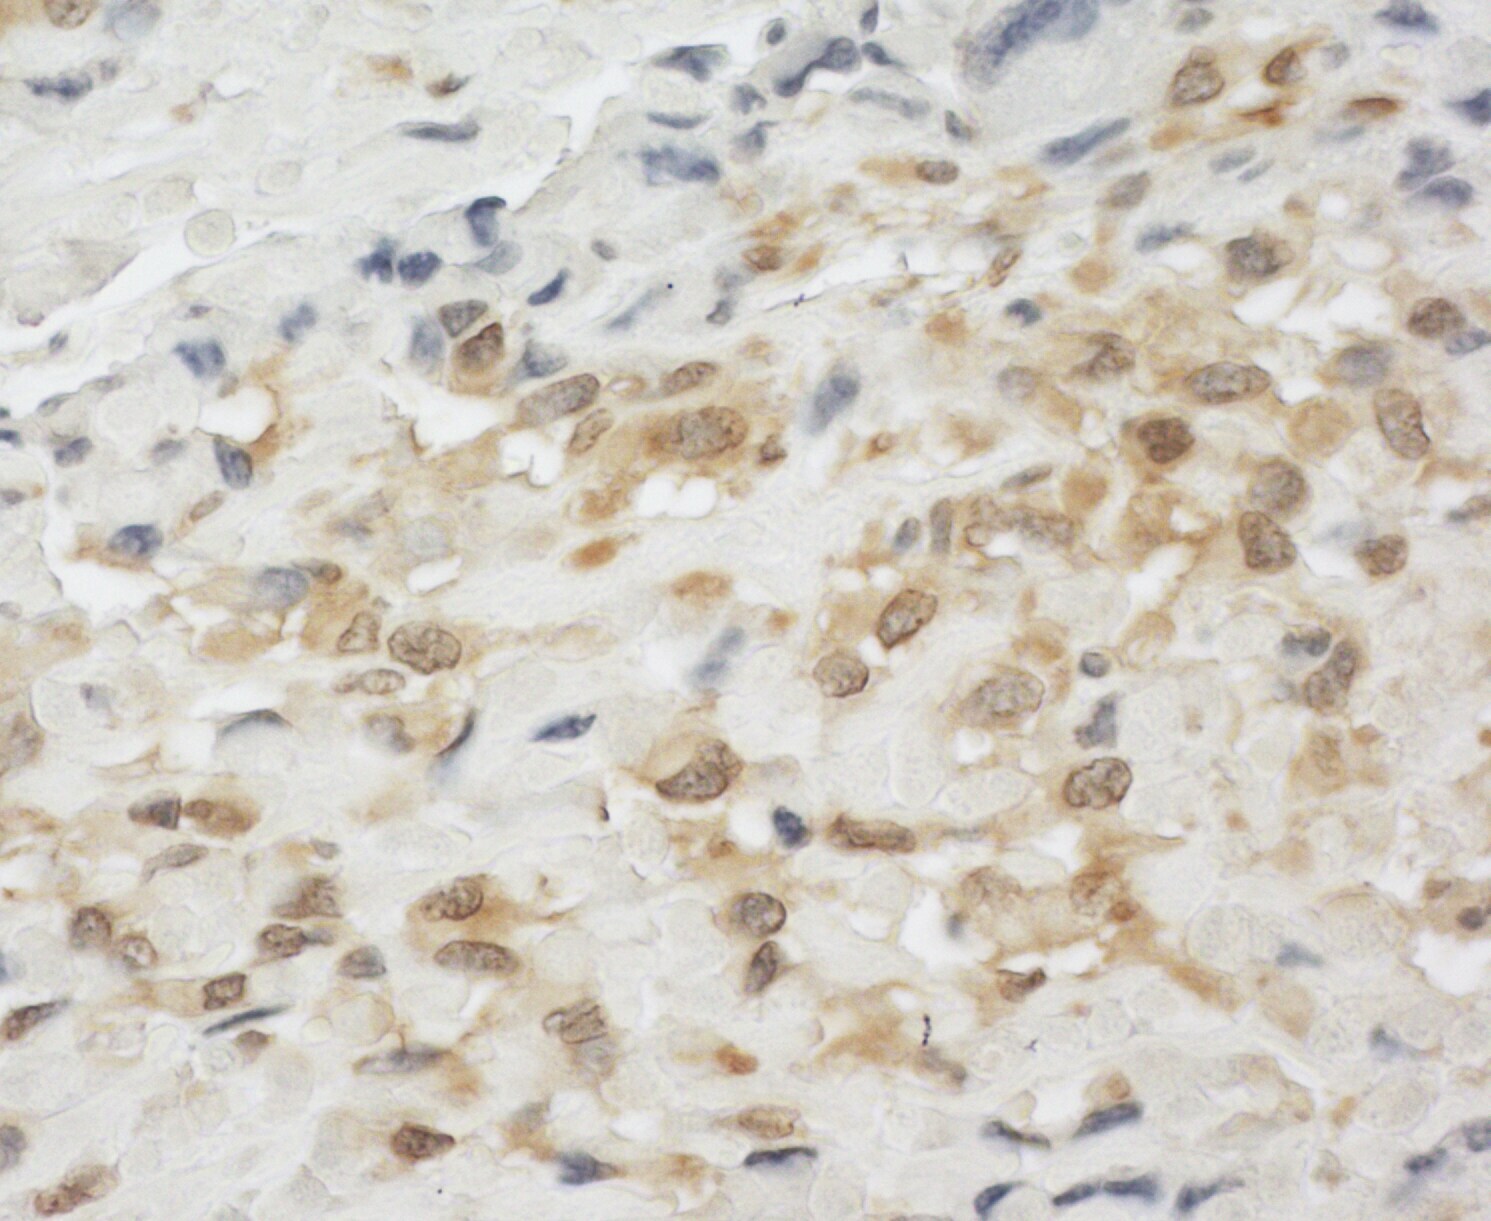

Supportive validation

- Submitted by

- Invitrogen Antibodies (provider)

- Main image

- Experimental details

- Detection of human LPP by immunohistochemistry. Sample: FFPE section of human osteosarcoma. Antibody: Affinity purified rabbit anti-LPP (Cat. No. A302-634A Lot1) used at a dilution of 1:200 (1µg/ml). Detection: DAB.